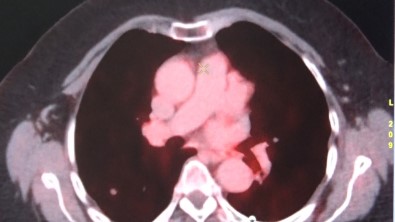

Kömek, “FDG PET/CT ile onkolojik tüm vücut görüntüleme yapan cihazlarimiz mevcut. Prostat kanserleri için 68Ga-PSMA, nöroendokrin tümörleri görüntülemesi için 68Ga (Galyum68)-Dotatate ve ülkemizde birkaç merkezde uygulanan TITCK (Türkiye Ilaç ve Tibbi Cihaz Kurumu) onayli oldugumuz FAPI (fibroblast aktivasyon protein inhibitörü) ile kolorektal ve gastointestinal kanserlerinin periton yayilimlarinda kullandigimiz FAPI görüntülemesi yapmaktayiz” dedi.

Hastanede yilda 6 bin hastanin tümör taramasi amaciyla PET/BT görüntülemesinin yapildigini söyleyen Kömek, “Hastanemizde ayrica tiroid kanseri 300 hastaya Iyot tedavisi yapilmakta. Yilda 400 hastaya da Lutesyum tedavileri, prostat kanserlerinin nöroendokrin tümörlerinin ya da agri palyasyonu amaciyla uygulanmaktadir. Açilimini yaparsak eger, radyoaktif madde ile isaretlenmis bir reseptör baglacini hastanin vücuduna enjekte ediyoruz ve sadece tümörlü alanlari tutup tedavi ediyor. Herhangi bir yan etkisi olmadan sadece tümöre spesifik reseptörlere baglanarak tedavi edildigi için, hedeflenmis radyoterapi dedigimiz sistemi kullaniyoruz. Bunun yani sira yilda yaklasik 300 hastanin da hipertiroidi tedavisini yapmaktayiz” seklinde konustu.